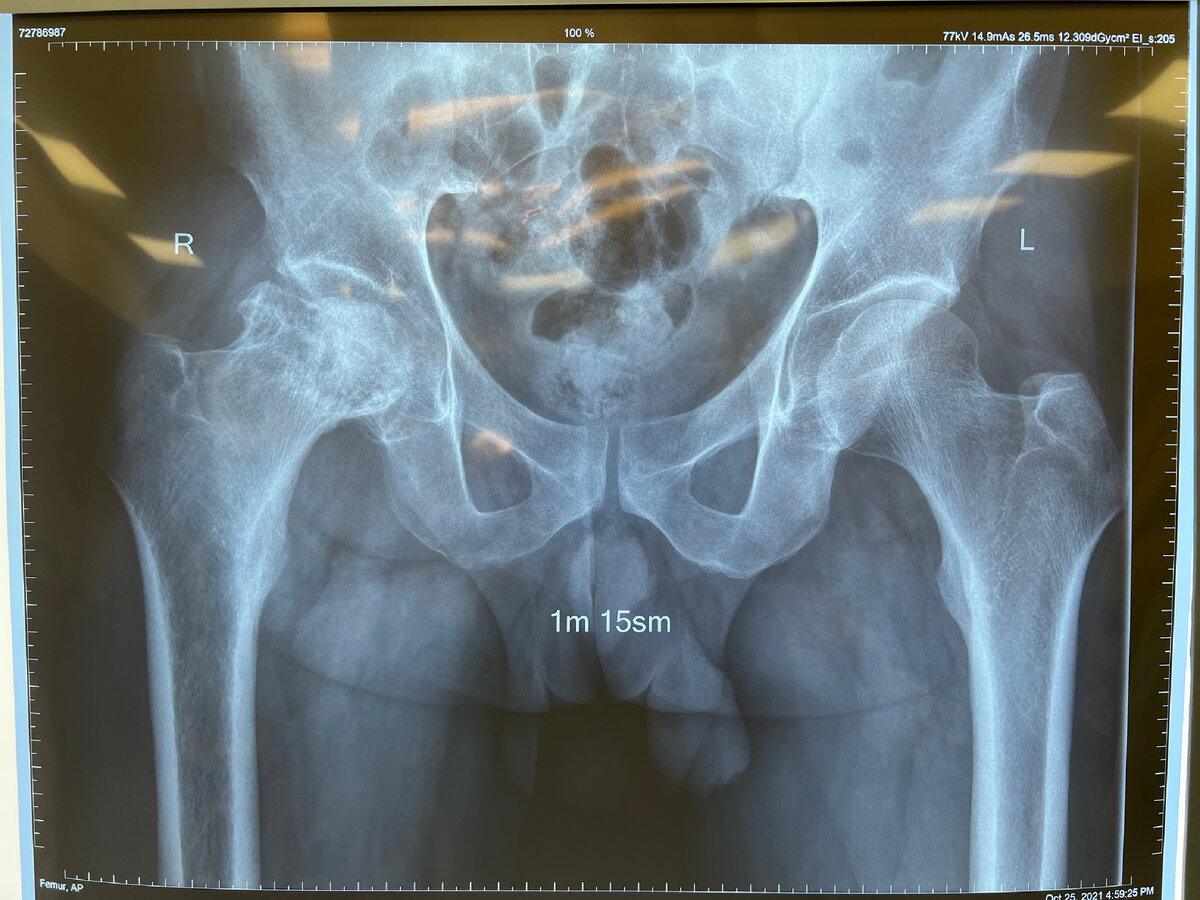

Асептический некроз головки бедренной кости.

Асептический некроз кости (остеонекроз) - это тяжелое заболевание, связанное с гибелью костных клеток в определенном участке костной ткани, с нарушением кровоснабжения, быстро приводящее к развитию вторичного артроза/артрита прилежа щего сустава. Наиболее частой локализацией является головка кости, на втором месте по распространению находятся мыщелки бедренной и большеберцовой костей, реже головка плечевой кости, таранная кость. В поздних стадиях и при выраженных болевых симптомах, показано оперативное лечение! Лечение по ОМС в частной клинике. #dr.bondorenko

Асептический некроз кости (остеонекроз) - это тяжелое заболевание, связанное с гибелью костных клеток в определенном участке костной ткани, с нарушением кровоснабжения, быстро приводящее к развитию вторичного артроза/артрита прилежа щего сустава. Наиболее частой локализацией является головка кости, на втором месте по распространению находятся мыщелки бедренной и большеберцовой костей, реже головка плечевой кости, таранная кость.

В поздних стадиях и при выраженных болевых симптомах, показано оперативное лечение!